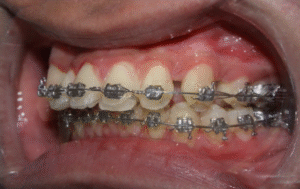

What Is Braces Bonding? Understanding the Process Behind Your Orthodontic Treatment

Ever wondered what braces bonding actually is and why it's so crucial to your orthodontic treatment? This essential process involves attaching brackets to your teeth...